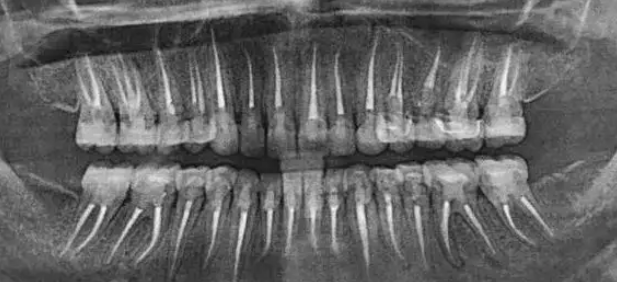

拔牙热知识:术前多读片,阻力牙才不会变压力!